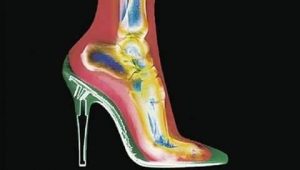

La malattia di Haglund si sviluppa lentamente nel corso degli anni e si manifesta con dolore e difficoltà motorie in età adulta. Si manifesta con una protuberanza ossea che si forma sulla parte posteriore del calcagno e provoca l’infiammazione delle borse sierose che proteggono il tendine d’Achille dallo sfregamento osseo. Nei casi in cui la malattia non venga curata in tempo, si creano delle callosità attorno la protuberanza, che spesso entra in conflitto con le calzature provocando lesioni e ferite della cute. Colpisce più frequentemente donne e sportivi, a causa del tipo di calzature indossate e dello sforzo a cui viene sottoposto il tallone. Corridori, maratoneti e marciatori sono gli sportivi più soggetti allo sviluppo del morbo di Haglund. Le cause del morbo di Haglund possono anche essere di tipo genetico, ma sono meno frequenti di quelle funzionali.

Quando il morbo di Haglund è nella fase infiammatoria acuta, può essere dolente al tatto o allo sfregamento, tanto da non permettere di indossare calzature con un bordo alto o comunque rigido.

- Problematiche funzionali dovuta ad una eccessiva sollecitazione: caratteristica dello sportivo o di alcuni lavoratori che fanno uso di scarpe non adeguate (anti infortunistica per esempio). Nei casi in cui è richiesta una intensa attività fisica per cui il tendine di Achille che si inserisce proprio sul calcagno, subisce dei microtraumi da trazione, con il risultato che tali microlesioni, vengono riparate dal corpo apponendo calcio, e quindi portando alla formazione dell’esostosi. Questa situazione è chiaramente legata ad uno sport, ma in alcuni casi anche lavori usuranti possono essere causa di questa sindrome.